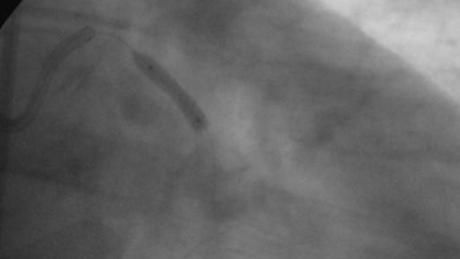

Bild 3: Nach der Ballonaufweitung ist das Gefäß wieder vollständig von Blut durchflossen und stellt sich in seiner ganzen Größe dar.